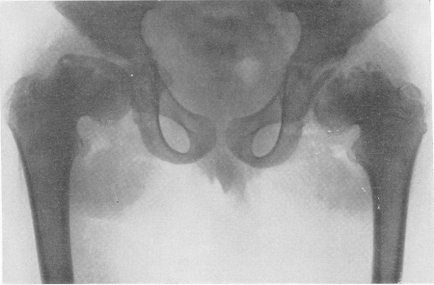

Fig. 278. Același pacient. X-ray a regiunii pelvine. Imaginea, care amintește de osteochondropatie bilaterală.

Este exprimat în diferența de femur înălțime epifizelor, și anume înălțimea epifizei femural medial semnificativ deasupra genunchilor laterale divergente și cu litera „X“. Capul fibulei este la un nivel normal și, prin urmare, nu participă la formarea articulației genunchiului.

Raza X a regiunii ambelor articulații genunchiului. Fibula este la o înălțime normală. Trebuie să presupunem că, atunci când osteohondrodistrofii scurtarea oaselor și prioskhodit, în esență, prin reducerea înălțimii epifizei, nu scurtarea metadiafiză. Contururile exterioare ale epifizelor sunt zdrobite și chiar erodate. Nucleul separat de osificare este împărțit, împărțit în părți, fragmentat, adică apar o mulțime de insule neregulate fără formă de osificare. Când epifizele se dezvoltă odată cu vârsta, ele "maturează", structura lor este încă oarecum ordonată, dar deformarea rămâne stabilă și ireversibilă. Late și subliniate sub forma benzilor dense ale zonei de osificare preliminară (figura 274). Oasele tubulare mici au fost, de asemenea, schimbate. Falajele sunt ușor scurtate și îngroșate, substanța lor spongioasă are o structură specială de plasă fină (figurile 275 și 276). Rata de osificare în seria noastră de cazuri este oarecum încetinită, nucleele de osificare în cazuri normale apar cu o mică întârziere. Pseudoepifizele se pot dezvolta. De aceea, la copiii mici, intervalele dintre metafiză ale oaselor opuse sunt mari - raze X articulate, uneori aproape de două ori mai largi decât cele normale. Fuziunea finală a epifizelor cu diafiză are loc cu deviații de la timpul normal în ambele direcții, uneori cu fluctuații mari. Modificări deosebit de mari se observă la copiii de vârstă școlară, apoi mai devreme, apoi mai târziu, în oasele articulației șoldului (Figurile 277 și 278). Capul epifizal al coapsei se poate să aștepte mult timp. Apărând, ea la o anumită vârstă tinerească dobândește o formă și o structură neregulată. Se mărește în mărime, aplatizează și se extinde, se împarte în multe aglomerări neregulate în formă de cartiere terestre.

Gâtul șoldului este foarte scurt și se îngroațește, scutul mare este deplasat ridicat, cu alte cuvinte, se dezvoltă deformația varus. Acetabulul dobândește, de asemenea, o formă neregulată, se extinde, aplatizează și deformează, articulațiile articulației șoldului își pierd corespondența reciprocă. Toate acestea fac schimbările în osteochondrodystrofie foarte asemănătoare cu osteochondropatia capului femural. Taz ca un întreg este în curs de asemenea abatere de la normă, el aruncă înapoi, stors din părțile laterale și în cazuri deosebit de grave osteohondrodistrofii inel pelvin aproape de forma inimii carte notorii sau un pahar de vin. Pentru regiunea articulației genunchiului, semnul distinctiv al articulației genunchiului este, așa cum sa menționat deja, deformarea valgus.